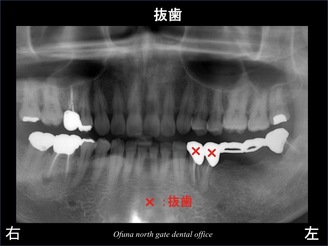

以下のレントゲンが初診時です。

診査の結果、下顎左側の奥歯が歯根破折 していました。

歯根破折 していた下顎左側の2歯は 抜歯と診断しました。

治療後が以下のレントゲンになります。